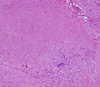

- What is adenomyosis?

- What are the histological changes?

- What is the clinical sign?

- Growth of endometrium in the myometrium

-

Histology:

- Enlarged, nodular myometrium with cysts

- Hemorrhagic cysts in functional endometrium

-

Clinical Signs:

- Abnormal uterine bleeding

- Infertility